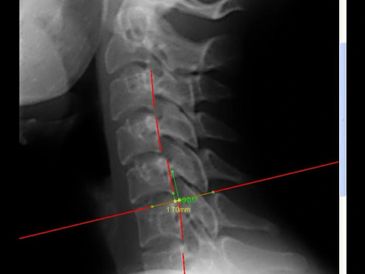

The two images of the patient above are identical. The one on the left is the original image and the one on the right has been enhanced. With digital radiography, we are able to take an image and zoom in, make it lighter or darker and add measurements. This allows us to see things that we might not be able to see on a conventional x-ray film. Instead of having to wait to develop the x-ray, it is on the screen within 30 seconds! With digital x-ray technology, we can take x-rays with less radiation dose to the patient. Finally, we can also put your x-rays onto a USB drive so you can have a copy for your records and can take them to other healthcare providers if needed.